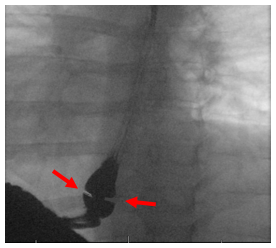

Narrowing can occur both at the top and bottom part of the esophagus. The most common benign type of esophageal narrowing is called a peptic stricture due to acid reflux. These strictures occur in the lower part of the esophagus. Other common types of benign narrowing include esophageal webs or rings, which are thin bands of scar tissue within the lining of the esophagus. Webs are commonly seen in the upper part of the esophagus and rings are commonly seen in the lower part of the esophagus.

Diagnosis of esophageal strictures is made by several evaluations including modified barium swallow study, barium esophagram, and transnasal esophagoscopy.Upper Esophageal Strictures and Webs Treatment

| Upper Esophageal Web | Schatzki Ring |